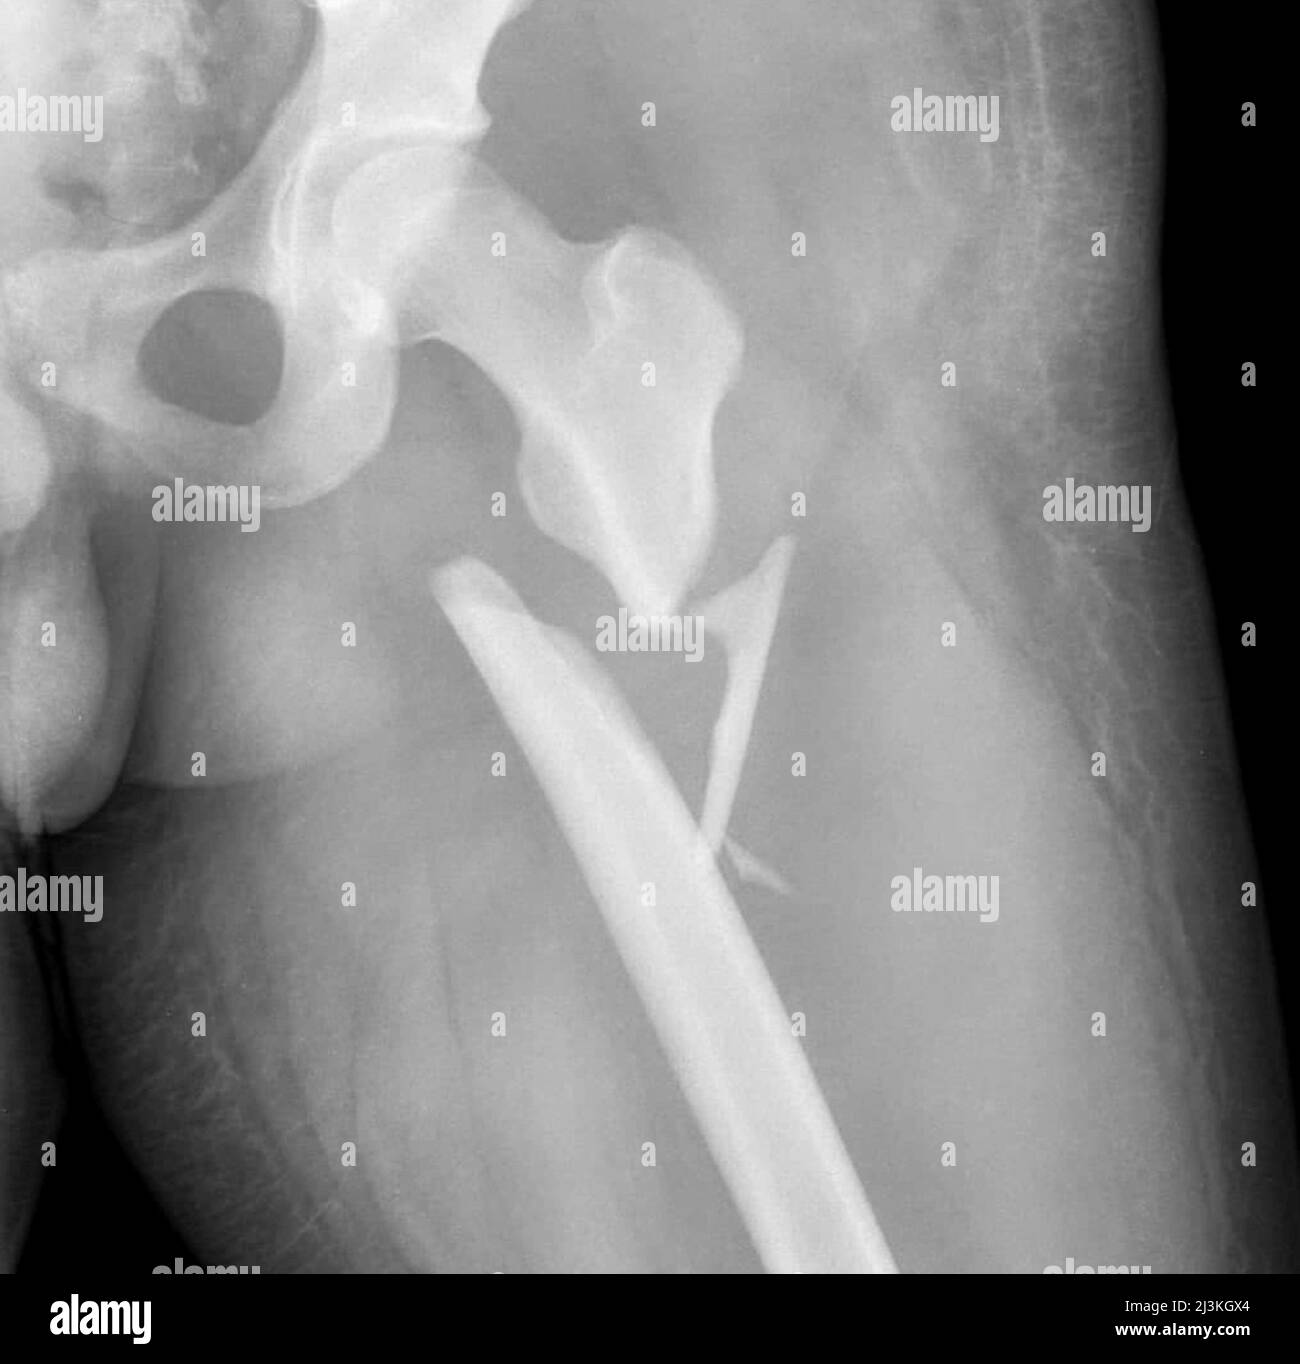

Перелом Бедра Фото Рентген

Перелом Бедра Фото Рентген 138 фото